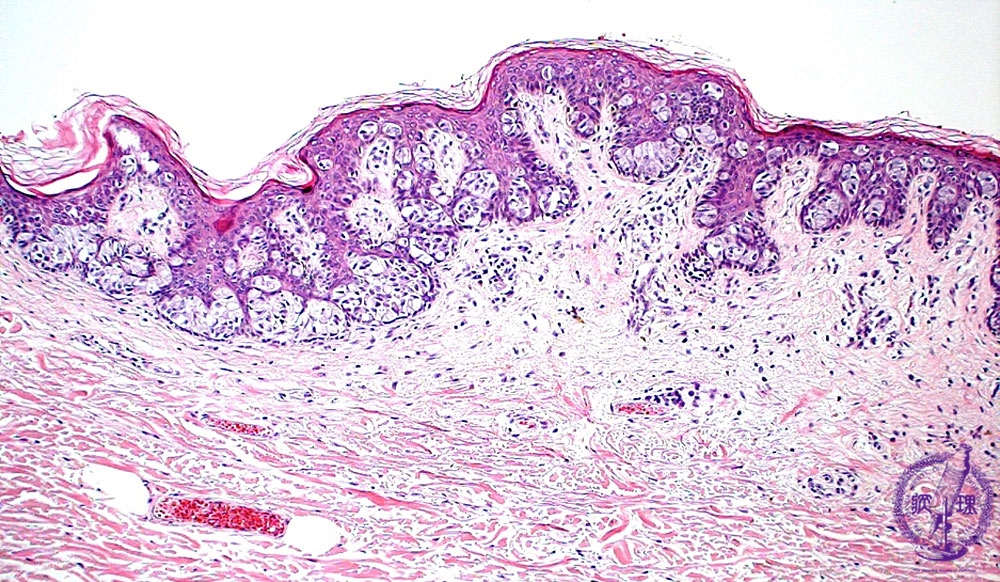

Microscopic image(HE stain, low power view):Duct-derived adenocarcinoma cells (Paget cells) propagated in epidermis. Those cells are large with clear and abundant cytoplasm.